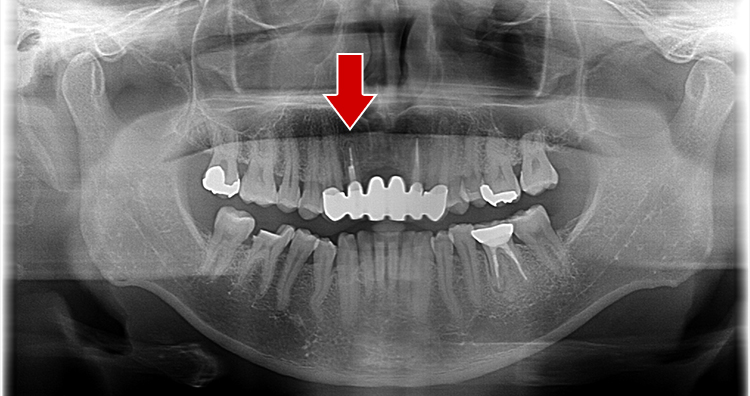

超最難関case(根尖病巣+パーフォレーション(術者のミス)

通常は「抜歯が当然」のcaseですが抜歯なしで治療成功事例

右下の画像が一番変化を診る上で基準となる画像でして(CT)、根の先端の病気が減っていること、白く濃く映った根のお薬がしっかりと入っている事が分かると思います。根の途中の黒い穴は、最初のドクターが謝って穴をあけてし合った後です。こういった高度な治療もセカンドオピニオンとしてお受けしております。

治療前

治療中

治療1年後

治療後3年後

レントゲンで施術前と施術後の比較

・赤色の部分→ドクターのミスをした箇所になります「パーフォレーション」

→結果、、、そこから病気ができています。。。

→通常はこれだけで「抜歯」となります。。。

・黄色の部分が根尖の病巣です。

→この原因でも抜歯となることもあります。

こちらの症例に関しても抜歯するくこともなく、治療成功となります。